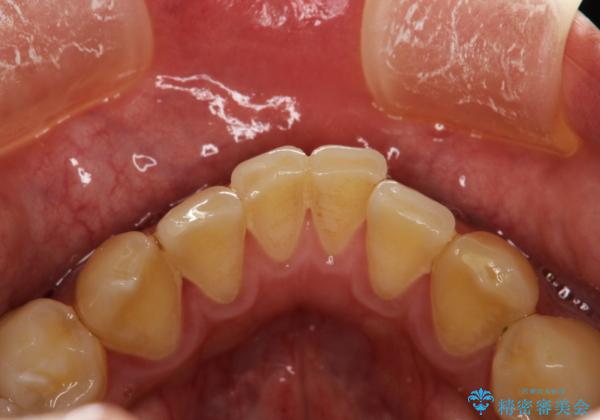

PMTCで歯の着色落とし

- 歯の着色・汚れが気になるとのことでクリーニンング希望とのことでした。PMTC30分コースを行いました。

プラーク(細菌の塊)や歯石がたまると歯の表面はザラつきいてきます。そのザラつきは歯周病や虫歯菌の棲家となります。そのまま放置すると、歯肉が腫れてきたり、歯肉から出血したり、口臭が強くでたりします。とくに歯肉の境目は、歯磨きで汚れを除去することが難しく、プラーク(細菌の塊)や歯石が溜まりやすい場所です。

歯並が、がたついている場合はなおさら汚れが溜まりやすいです。矯正治療前や定期的にPMTCをすることで、歯肉トラブルを防ぐことにつながります。